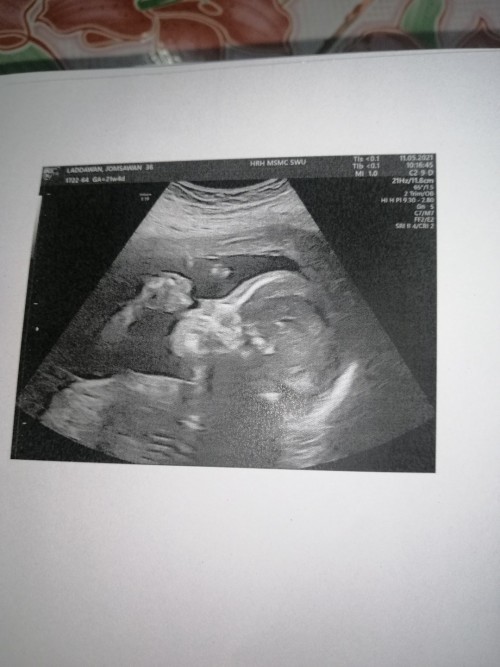

12Wค่ะ

3เดือนแล้วค่ะ..เริ่มเห็นแขน ขา บ้านใหนเหมือนกันมั๊ยค่ะ???3เดือนเห็นชัดขนาดนี้เหมือนกันรึป่าวค่ะ

ตอนซาวท้องตอน3เดือนจ้า